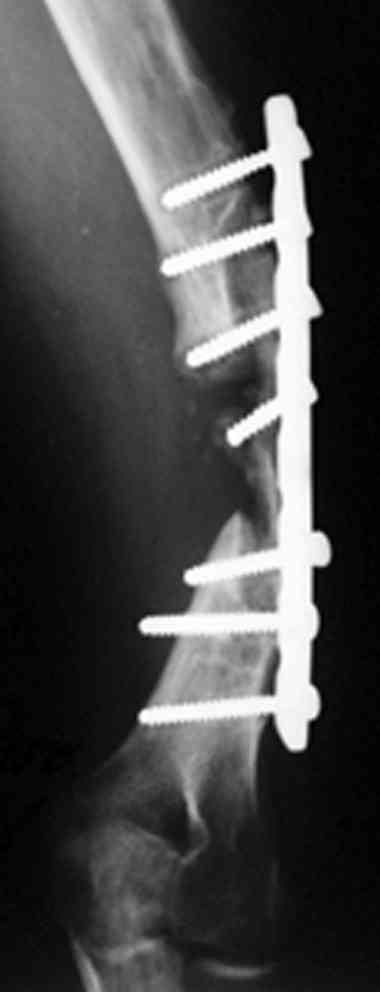

На примере два случая, извиняюсь за качество снимков, снимки и случаи из бывшего союза.

Первая больная с "успехом" была прооперирована 6 раз различными методами открытого и закрытого

остеосинтеза, включая то, что в Кисловодске заезжим австралийским "кудесником" на ложный сустав уложена скорлупа от страусиновых яиц. Последняя операция одиноким локинг плейт в одной из клиник.

Через год по поводу тех же проблем сделали ревизию, оригинальную пластину оставили как есть, только укрепили добавлением еще одной пластины и сделали костную пластику.

Через два месяца увидели признаки консолидации.